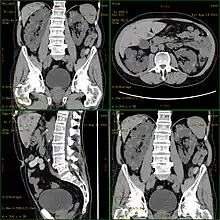

CT scan showing autosomal dominant polycystic kidney disease

Polycystic kidney disease can be ascertained via a CT scan of abdomen, as well as, an MRI and ultrasound of the same area. A physical exam/test can reveal enlarged liver, heart murmurs and elevated blood pressure[1]